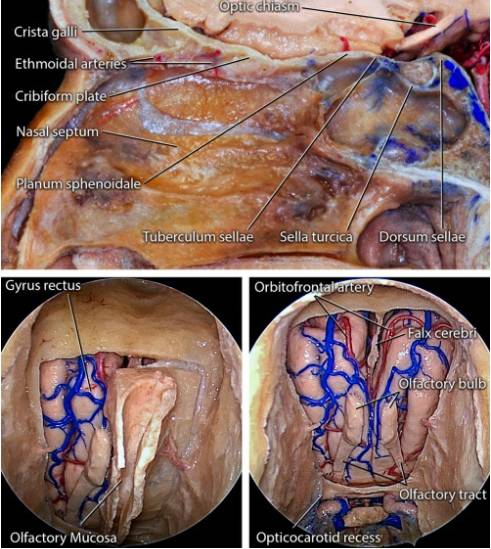

图2. 前、中颅底骨性解剖如上图所示,橘黄色箭头所指的前颅窝筛板及其后方就是典型的嗅沟脑膜瘤(OGM)的起源(图片来自AL Rhoton,Jr)。2:前、中颅底骨性解剖如上图所示,橘黄色箭头所指的是典型的嗅沟脑膜瘤(OGM)的起源(图片来自AL Rhoton,Jr)。

图3. 嗅沟以及嗅沟与周围结构的解剖关系上面观。注意在轴位沿颅底中线解剖时眶顶的变化。在沿颅底阻断肿瘤血供时,应该记住这些解剖关系。术中主要出血来源于筛前及筛后动脉,经鼻内镜入路,在早期控制肿瘤基底这两组动脉,可以提高手术效率(图片来自AL Rhoton,Jr)。

图4:通过经鼻内镜观察到的嗅沟脑膜瘤的血管解剖,注意筛前和晒后动脉的位置(图片来自AL Rhoton,Jr)。下排图片显示了最终骨性暴露。

图5:通过经鼻入路,前颅底的解剖。矢状位图像显示不同的骨性标志。其他两张图说明了经筛板入路的相关手术解剖。